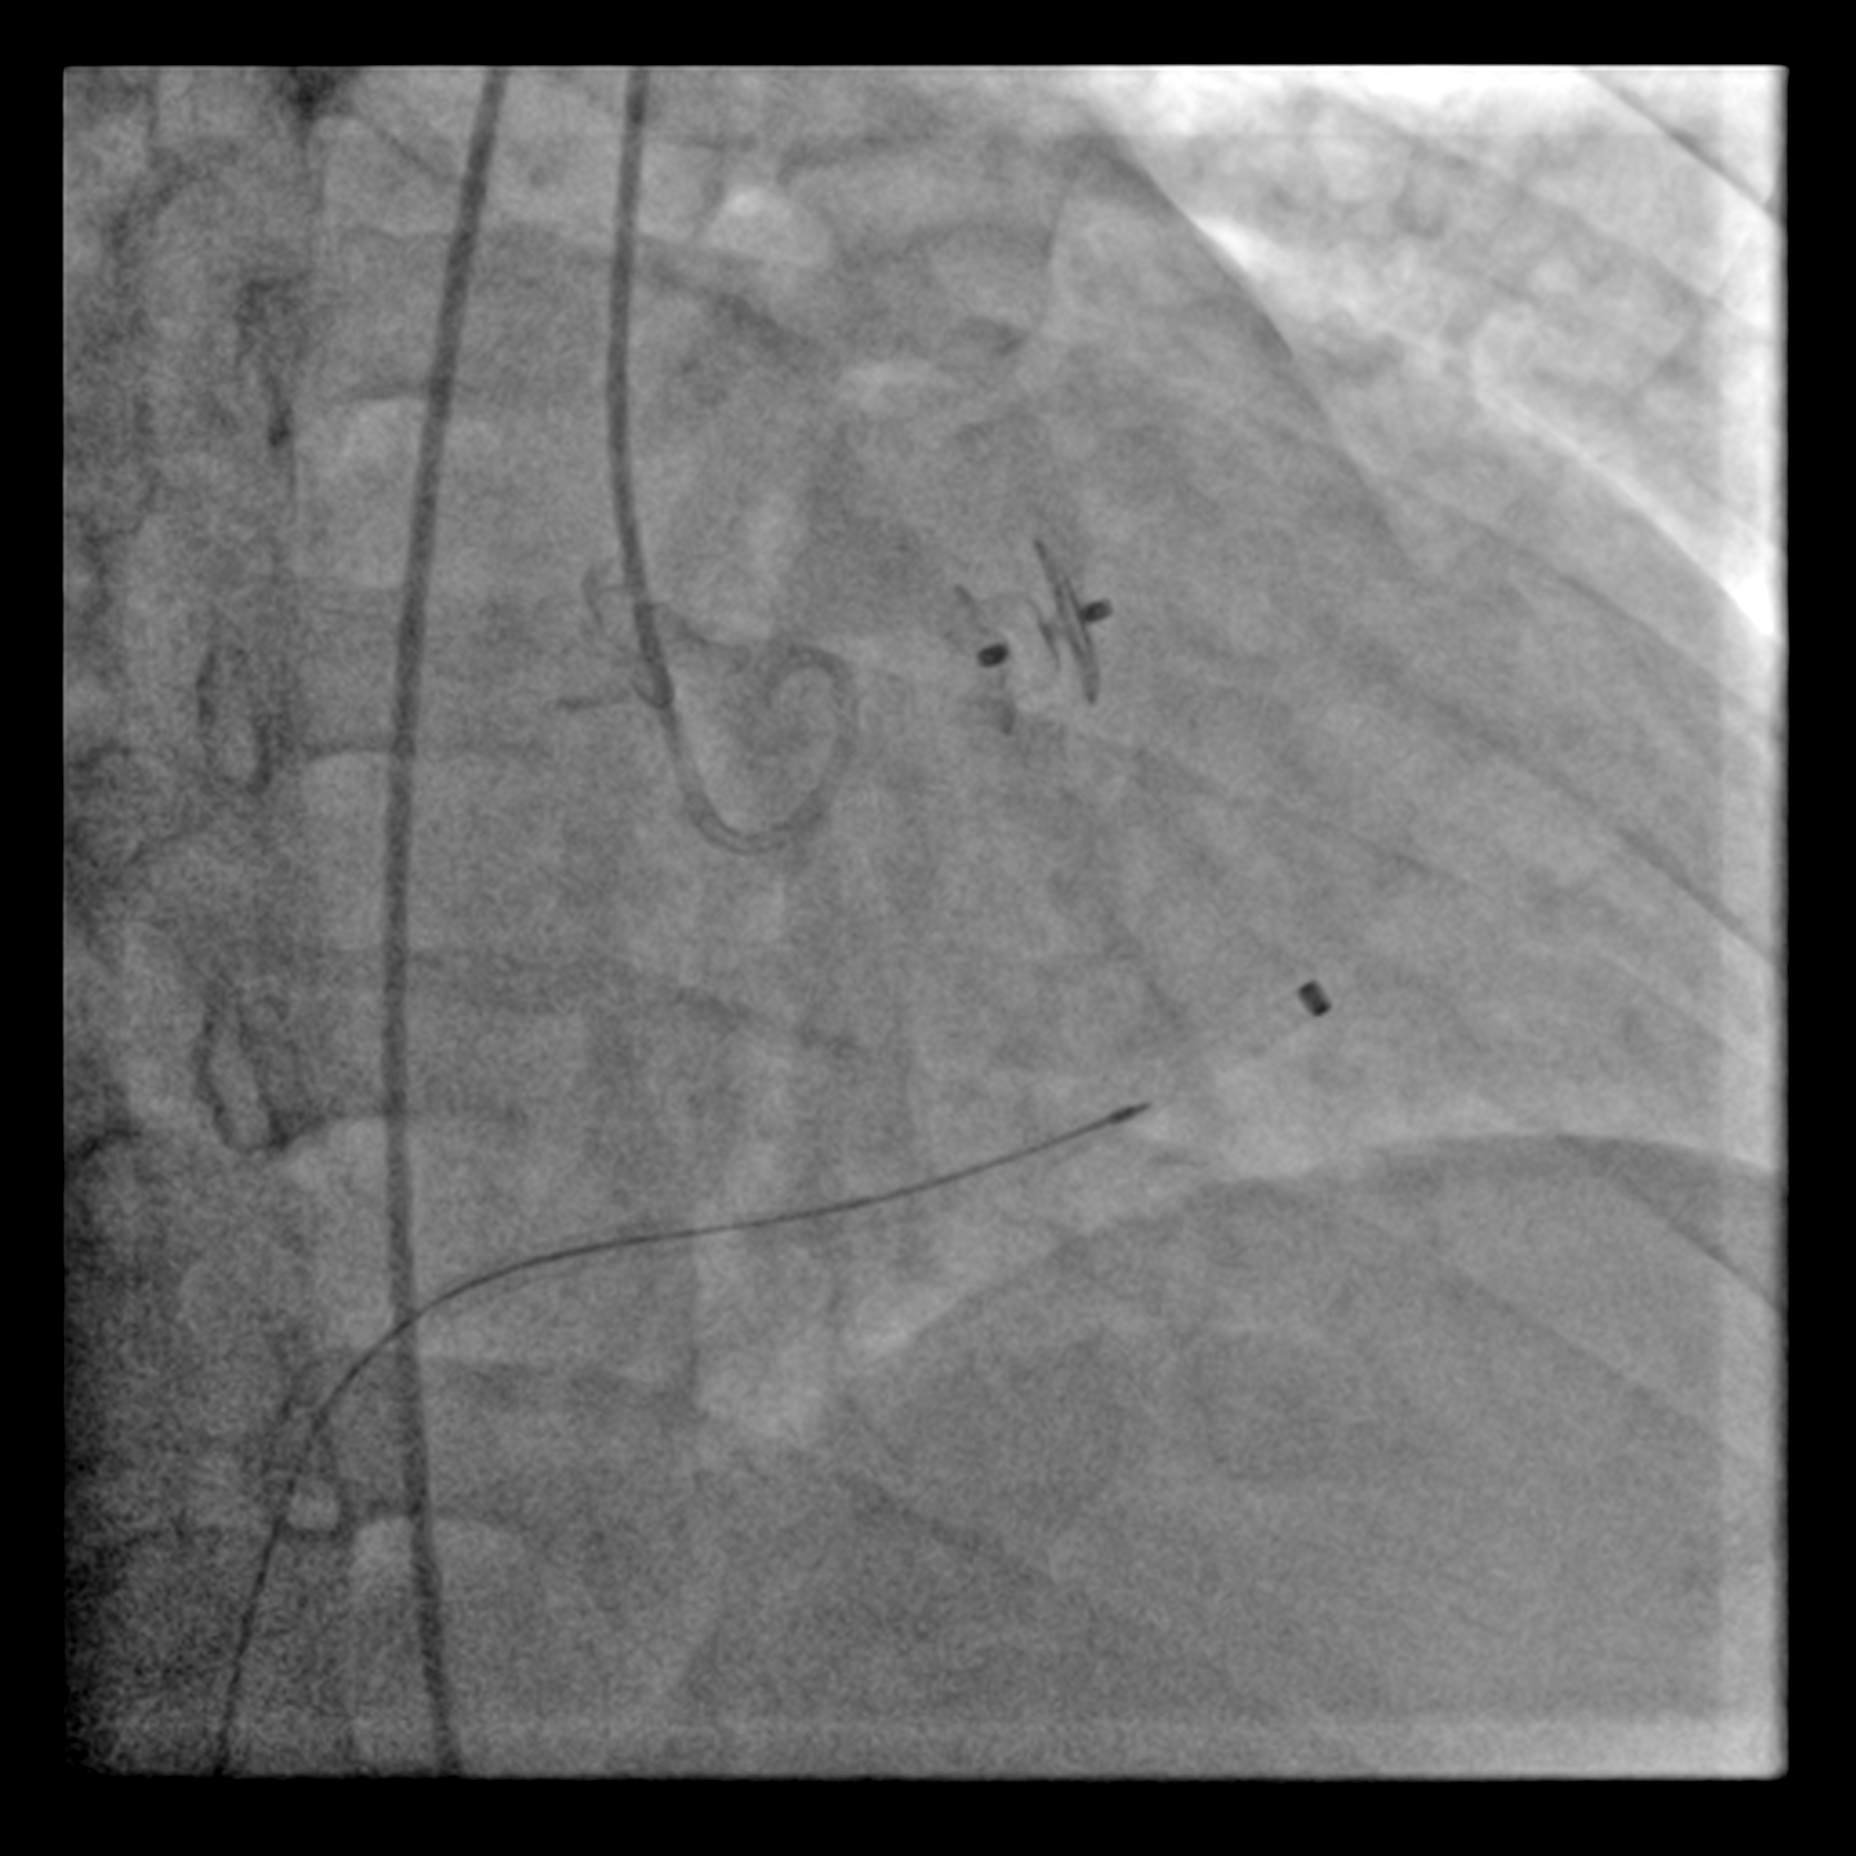

The procedure was commenced with one 7Fr sheath in right femoral vein & one 6Fr sheath in right femoral artery. From arterial access, a diagnostic Judkins right (JR) catheter 6Fr was positioned in right SOV. The defect was crossed with J-tipped Glidewire & subsequently advanced into right pulmonary artery. A Multipurpose (MPA) catheter was introduced via right femoral access & advanced into right pulmonary artery where the Glidewire was snared & externalised through the venous access. This created an arteriovenous wire loop. The delivery sheath was advanced over this loop wire, through the venous access, crossing the SOV's defect & positioned in ascending aorta. A 10-8mm KONAR-MFO VSD occluder (Lifetech) was smoothly deployed antegradely but left unreleased. A repeated non-selective aortogram was made with Pigtail catheter in ascending aorta confirmed preserved right coronary flow was & absence of aortic regurgitation. A trans-thoracic echocardiography confirmed the stable position & good defect sealing. The aortic valve demonstrated normal mobility without evidence of aortic stenosis & regurgitation. The occluder was then released under fluoroscopic guidance.